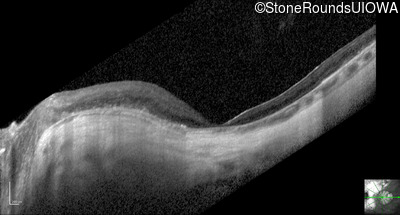

Optical Coherence Tomography - Left - 20/100 -1

Exemplar / OCT Stack

OCT Stack